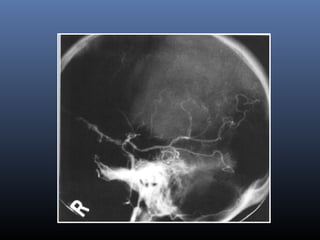

Conventional angiography-

Indications

 DSA IS USUALLY PERFORMED ONLYDSA IS USUALLY PERFORMED ONLY

WHEN ENDOVASCULAR THERAPY ISWHEN ENDOVASCULAR THERAPY IS

BEING CONSIDEREDBEING CONSIDERED

evaluation of carotidsevaluation of carotids

 To determine degree of stenosis

 To look for tandem lesions( carotid siphon,

horizontal MCA)

 Evaluate collateral circulation

acute infarcts

 Vessel occlusion- most specific

 Slow antegrade flow

 Retrograde filling

 Bare areas

 Mass effect

 Vascular blush

Moya- Moya Disease

 Progressive stenotic arteriopathy involving

proximal intracranial arteries

SUPRACLINOID ICA,

PROXIMAL ACA AND MCA

PCA RARELY, LATELY INVOLVED

HYPERTROPHY OF LENTICULOSTIATE

AND THALAMOPERFORATOR ARTERIES

Moya- Moya disease- Imaging

Pial synangiosis- Dilated superficial

temporal and middle meningeal arteries

 Infarctions-

 Intense enhancementof basal ganglia

 Enhancement of dilated deep medullary veins in

centrum semiovale

 Pial collateral enhancement

 DSA- Puff of smoke appearance